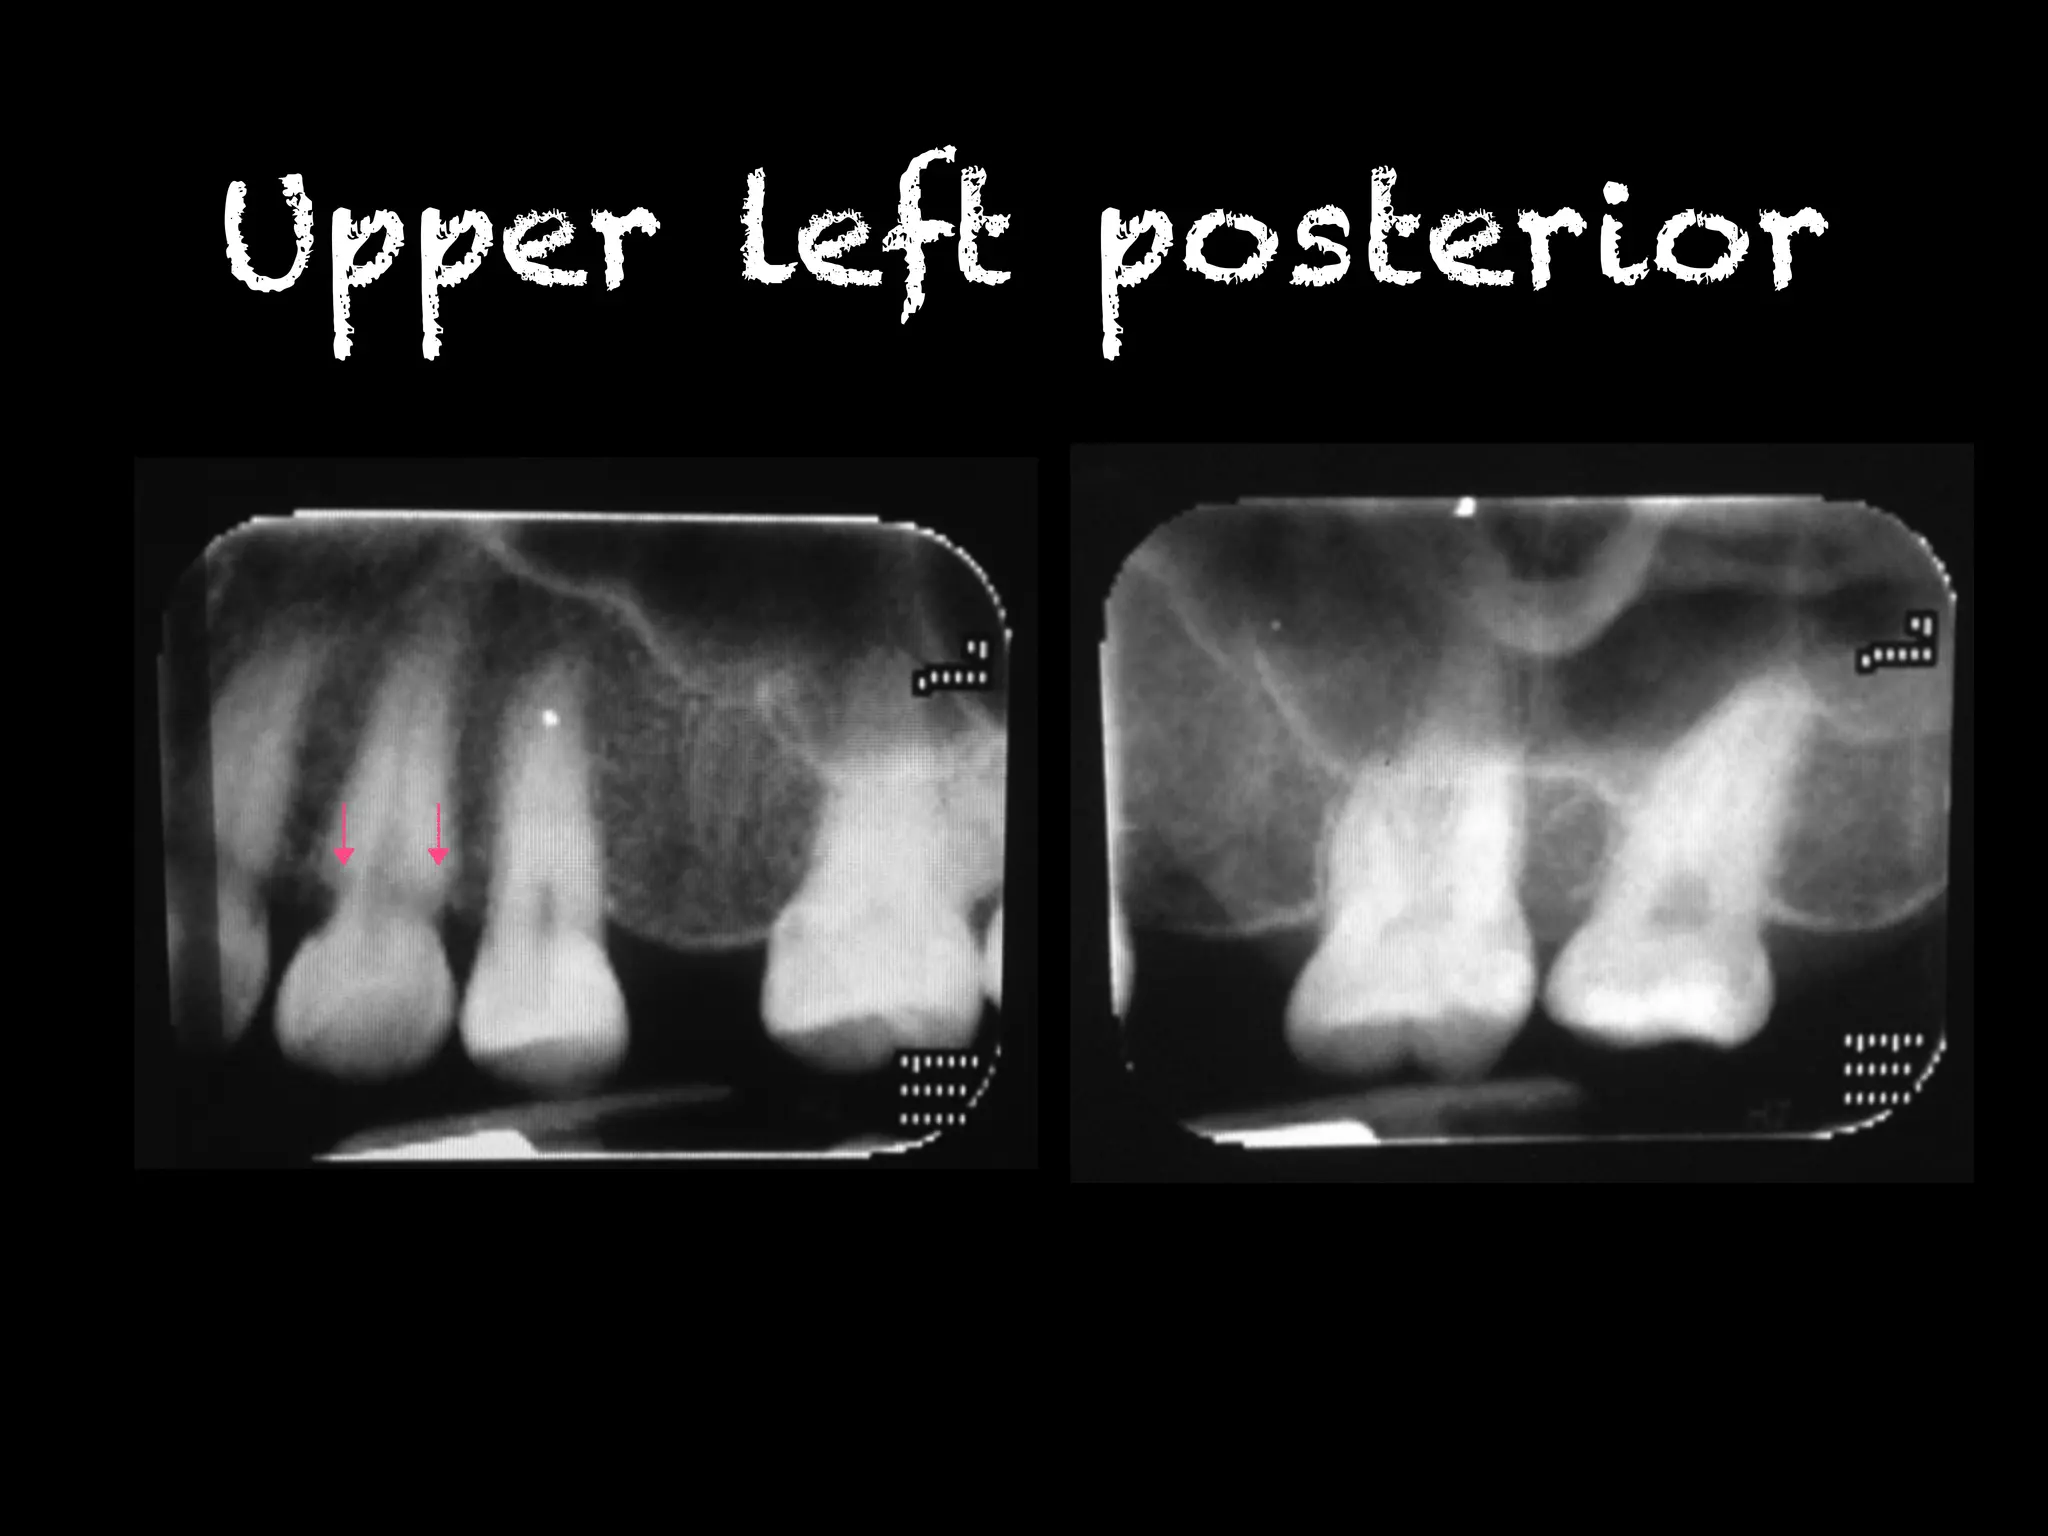

Upper left posterior

พบรอยโรคโปร่งรังสีที่บริเวณคอฟัน ฟันซี่

12MD,13M,22MD,23M,31MD,32MD,33MD,

41MD,42MD,43MD,34MD,35MD,36MD,

48M